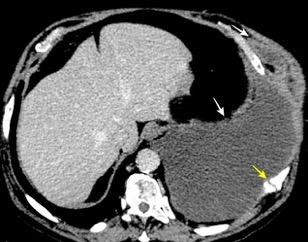

Naidich DP et al. Computed tomography of the diaphragm: peridiaphragmatic fluid localization.J Comput Assist Tomogr1983.

En el corte axial, el líquido pleural se sitúa por detrás